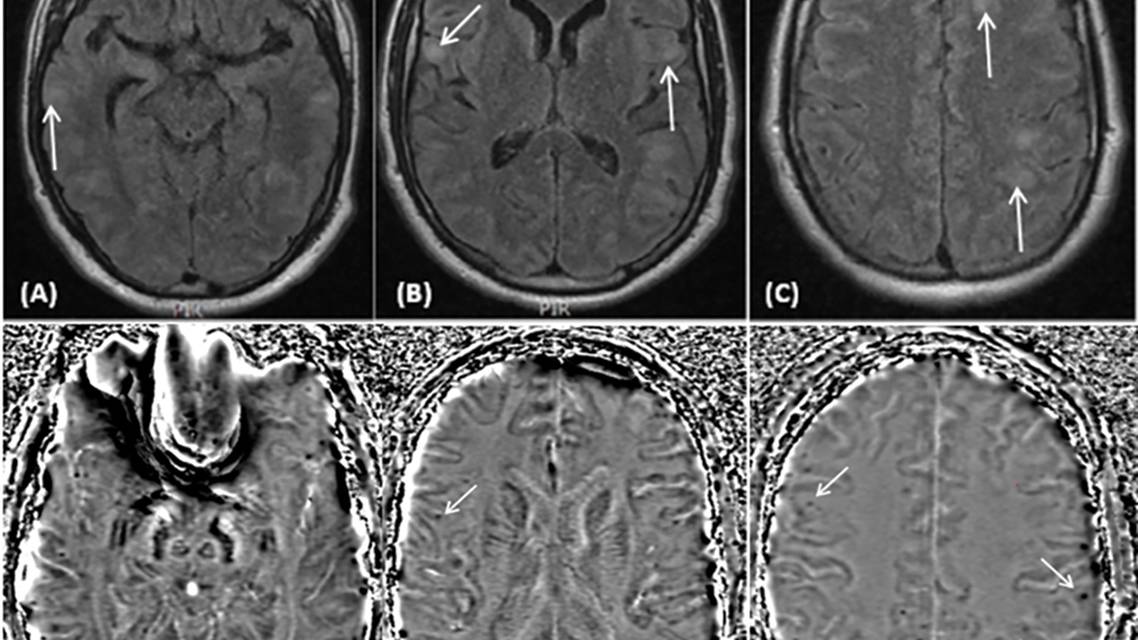

Initial laboratory testing demonstrated neutrophilia (27 x 109/L) but normal erythrocyte sedimentation rate and C-reactive protein level. CSF bacterial and fungal culture, and polymerase chain reaction for herpes simplex virus (HSV)–1 and HSV-2, varicella-zoster virus, Epstein-Barr virus, cytomegalovirus, and enterovirus, had negative results (Table 1). There were faint unmatched CSF oligoclonal bands. EEG demonstrated diffuse slow-wave activity without evidence of ongoing seizure activity. Brain MRI showed multiple subcortical fluid-attenuated inversion recovery (FLAIR) hyperintensities in the frontal, parietal, and temporal lobes bilaterally, and scattered subcortical microhemorrhages on susceptibility-weighted imaging (Figure 1). There was no restricted diffusion or gadolinium enhancement. Spinal cord MRI results were normal. Although there was no enhancement, the brain imaging results were consistent with a diffuse neuroinflammatory process and, given the cortical microhemorrhages, a diagnosis of cerebral amyloid angiopathy–related inflammation (CAA-ri) was considered.

Figure 1. Brain MRI on admission demonstrated diffuse subcortical fluid-attenuated inversion recovery (FLAIR) hyperintensities throughout the frontal, parietal, and temporal lobes bilaterally (A–C). Phase susceptibility-weighted imaging sequences demonstrated scattered subcortical microhemorrhages (D–F). The arrows point to examples of subcortical FLAIR hyperintensities and phase microhemorrhages.